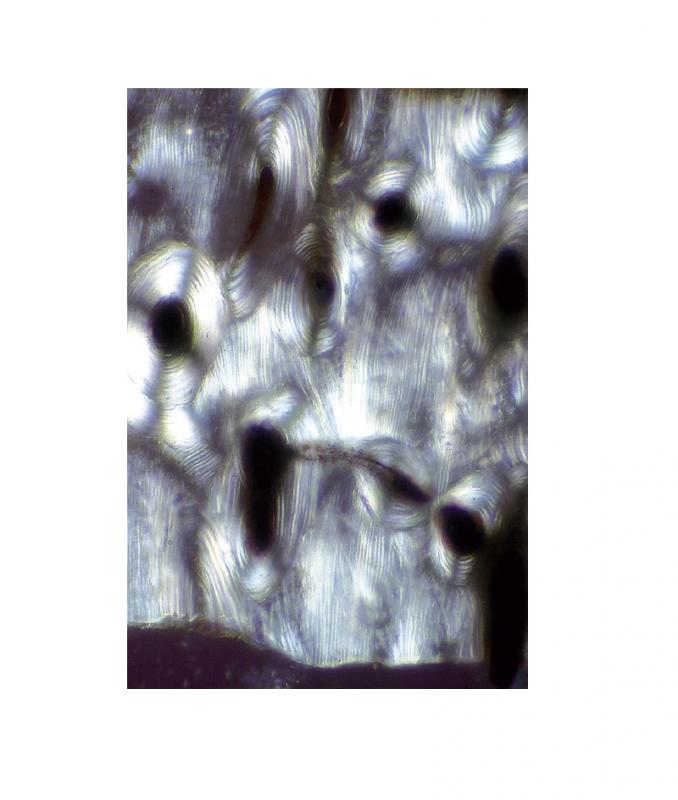

Préparation microscopique: Tissu adipeux CT

Tissus adipeux Coupe transversale (CT) Préparation microscopique - Biologie animale - Cythologie et histologies diverses À l'unité